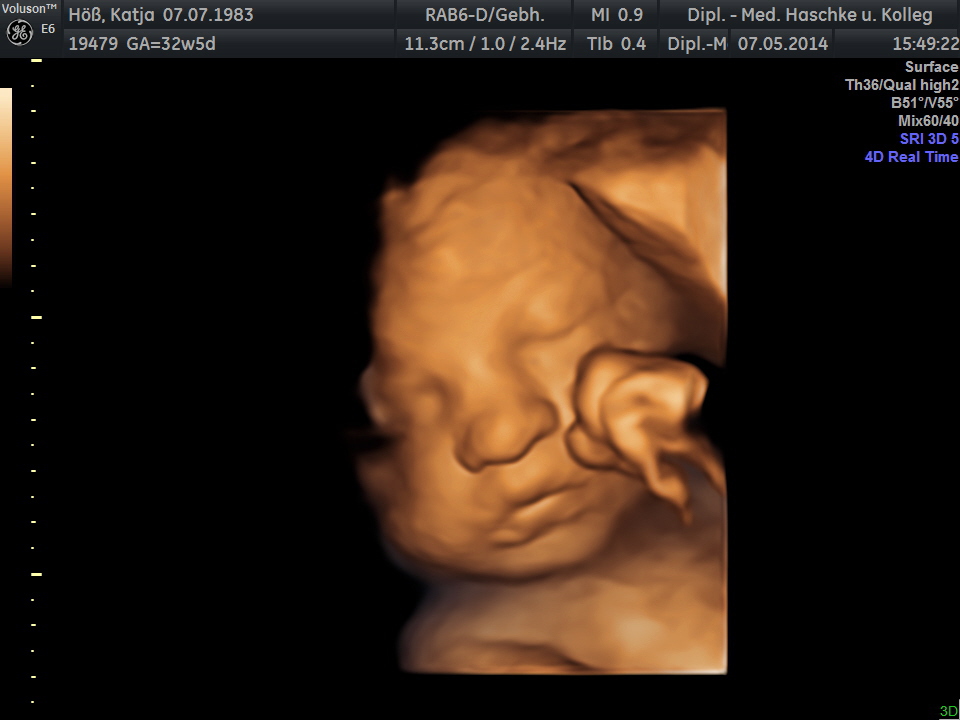

Schwangerschaftswoche 32

Heute ist der 7.5.2014 und 11.15 Uhr, wo wir wieder unsere Gynäkologin besuchten. Ich wurde dann ans CTG angeschlossen, wo die Herztöne des Babys und Wehen aufgezeichnet wurden. Das dauerte etwa eine halbe Stunde und laut Ärztin ist alles in Ordnung. Am Nachmittag sind wir dann nochmals in die Praxis gefahren, um 3D Bilder machen zu lassen. Das sind leider die letzten Bilder, es wird jetzt alle zwei Wochen nur noch das CTG durchgeführt. Die richtige Lage hat sie nun eingenommen.